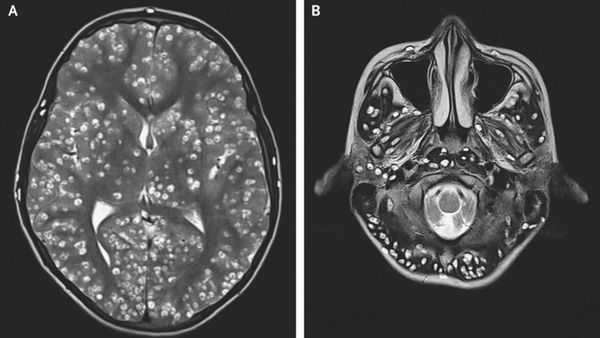

Во время рвоты в желудок больного тениозом могут забрасываться членики свиного цепня, содержащие инвазионные яйца. Освободившиеся из яиц онкосферы с кровотоком мигрируют по организму, оседая в мышцах и внутренних органах. Так происходит эндогенное заражение цистицеркозом – внекишечной формой тениоза, вызываемой цистицерками - личинками свиного цепня. По месту паразитирования цистицерков выделяют цистицеркоз головного мозга, глаз, кожи, сердца, легких.

На цистицеркоз мозга приходится 60% случаев внекишечного тениоза. Поражение больших полушарий сопровождается гидроцефалией и церебральной гипертензией. Больные испытывают приступы головокружения и головных болей, страдают расстройствами чувствительности, нарушениями речи, эпилептическими припадками. В эндемичных районах цистицеркоз является самой частой причиной эпилепсии среди местного населения. При цистицеркозе головного мозга могут отмечаться психические нарушения - возбуждение, депрессия, галлюцинаторно-бредовые идеи. В случае попадания цистицерков в желудочковую систему (чаще IV желудочек) мозга развивается синдром Брунса (интенсивные приступы головной боли и рвоты, вызванные изменением положения головы), нарушения сердечной деятельности и сознания. При цистицеркозе основания головного мозга развивается клиническая картина базального менингита, сопровождаемая рвотой, головной болью, брадикардией, поражением черепных нервов.

При локализации в головном мозге вокруг капсулы наблюдается воспаление мелких сосудов и инфильтрация окружающей ткани плазматическими клетками, что вызывает расстройство движения спинномозговой жидкости (ликвора), отёк мозговой ткани, развитие менингита и энцефалита. При паразитировании в оболочках мозга у его основания возможно развитие рацемозной (ветвистой) формы цистицеркоза до 25 см в длину.

Компьютерная (КТ) и магнитно-резонансная томография (МРТ), ультразвуковое исследование (УЗИ), прямая офтальмоскопия — применяются для выявления цистицеркоза. КТ лучше выявляет кальцификаты цистицерков (особенно небольшие). МРТ больше подходит для обнаружения цистицерков в некоторых трудновизуализируемых местах мозга, также МРТ указывает на местные окружающие изменения (отёк) и возможную гибель паразита.